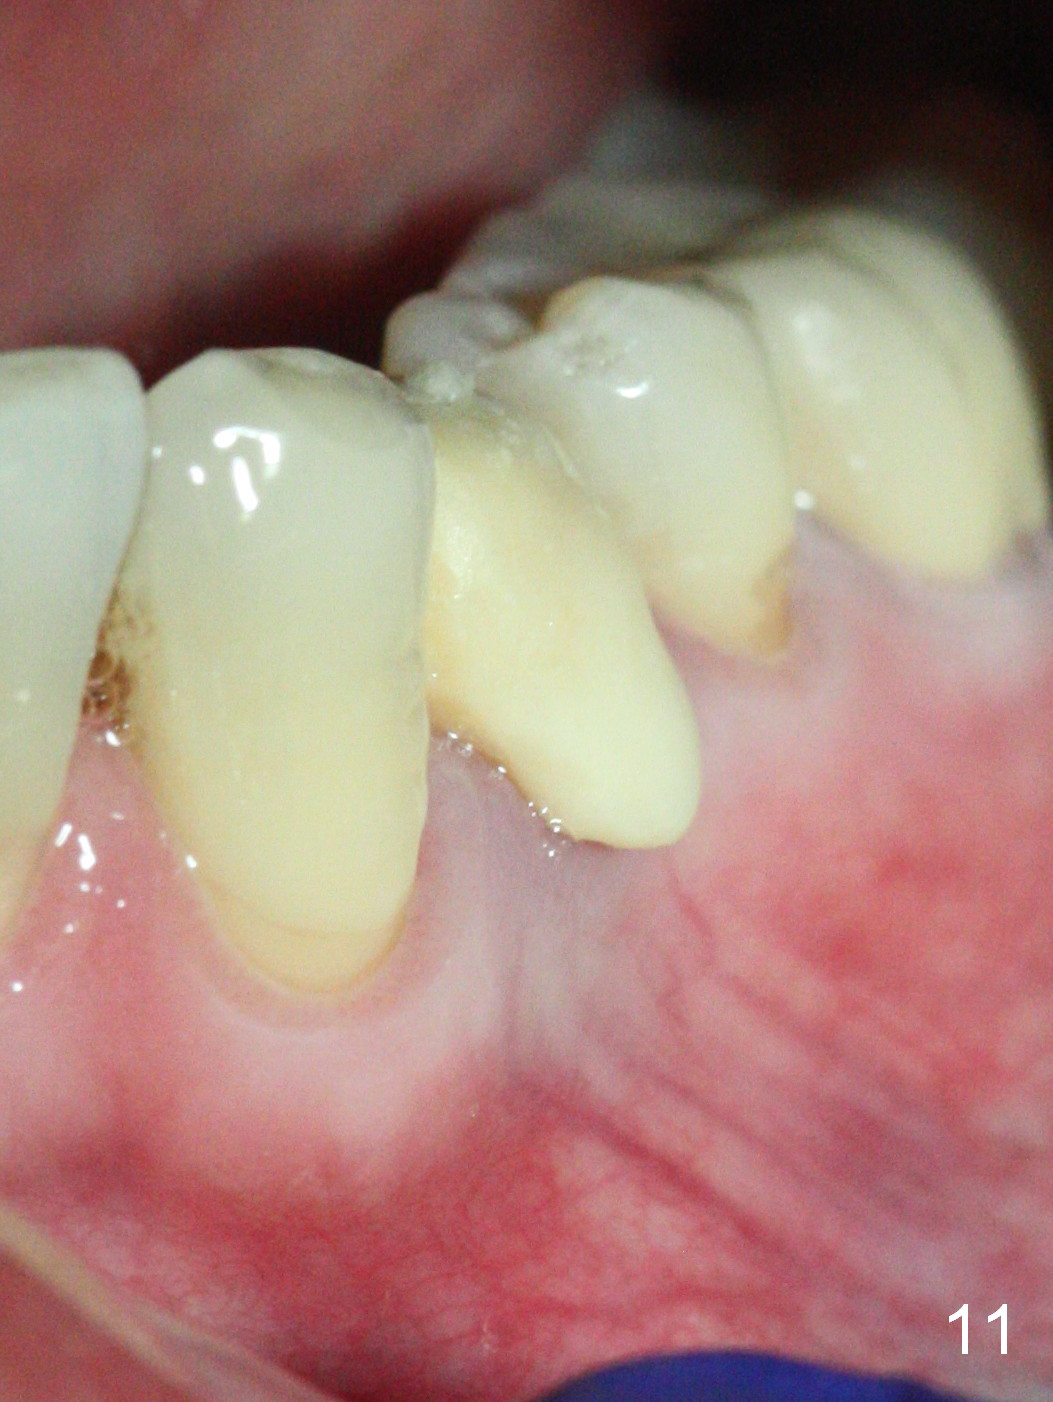

The implant seems to have osteointegrated 4 months postop (Fig.9).  When a permanent crown is fabricated, it should have normal occlusal and buccal contour (from Fig.11 (provisional) to 12 red and black curved lines) as well as the buccal cervical extension (Fig.12 to cover the buccal gingiva (Fig.10 *).  If the lingual margin of the abutment is too prominent, return the case and the abutment will be changed to the one with 2 mm cuff (existing 3 mm).  The lingual margin of the abutment will be trimmed.  The patient is not pleased with the short buccal margin of the crown after cementation (Fig.13).  In fact the provisional should have been fabricated so that the its buccal margin should be subgingival and within the gingival outline.  It may prevent buccal plate collapse.  In fact the crown dislodges 1 year post cementation.  The lingual margin is prep lower to increase the abutment height.  Impression is taken.  Although the access hole is unnecessary for cementation, it acts as an escape hole so that there is no excess cement cervically (Fig.14-18).